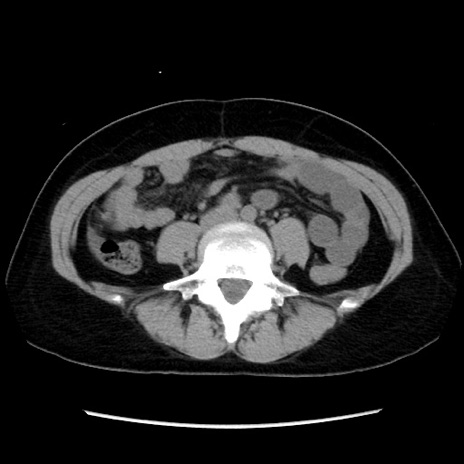

症例10(横断像)

【症例】 50歳代女性

【主訴】 腹痛

【現病歴】前日生レバーを食べた。今朝に排便あり。 昼前に突然発症の腹痛を生じ、当院救急外来を受診した。

【既往歴】 子宮筋腫にてで子宮全摘後

【身体所見】 意識清明、腹部:平坦、軟、下腹部やや左を中心に圧痛・反跳痛あり、筋性防御あり

【データ】WBC 7800、CRP 0.07